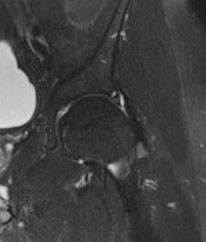

Question 2

A 75-year-old woman sustains a displaced femoral neck fracture after a mechanical fall. Which of the following is the predominant blood supply to the femoral head that is at risk of disruption in this injury?

Explanation

The predominant blood supply to the adult femoral head is provided by the lateral epiphyseal artery, which is the terminal branch of the medial femoral circumflex artery (MFCA). This runs along the posterosuperior aspect of the femoral neck and is frequently disrupted in displaced femoral neck fractures, leading to a high risk of avascular necrosis.